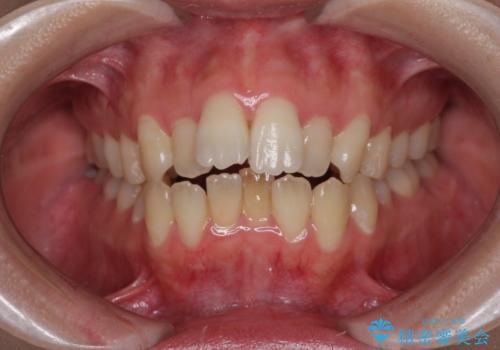

【ハーフリンガル】重度の叢生

担当医 河口智英